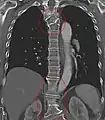

Short ribs at the first lumbar vertebra, which is thus a transitional vertebra, since lumbar vertebrae normally do not have ribs attached to them.

Transitional vertebrae have the characteristics of two types of vertebra. The condition usually involves the vertebral arch or transverse processes. It occurs at the cervicothoracic, thoracolumbar, or lumbosacral junction. For instance, the transverse process of the last cervical vertebra may resemble a rib. A transitional vertebra at the lumbosacral junction can cause arthritis, disk changes, or thecal sac compression. Back pain associated with lumbosacral transitional vertebrae (LSTV) is known as Bertolotti's syndrome. One study found that male German Shepherd Dogs with a lumbosacral transitional vertebra are at greater risk for cauda equina syndrome, which can cause rear limb weakness and incontinence.[10]